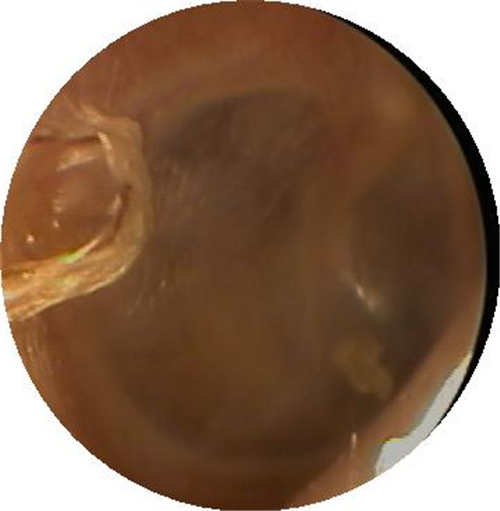

左耳鼓膜穿孔